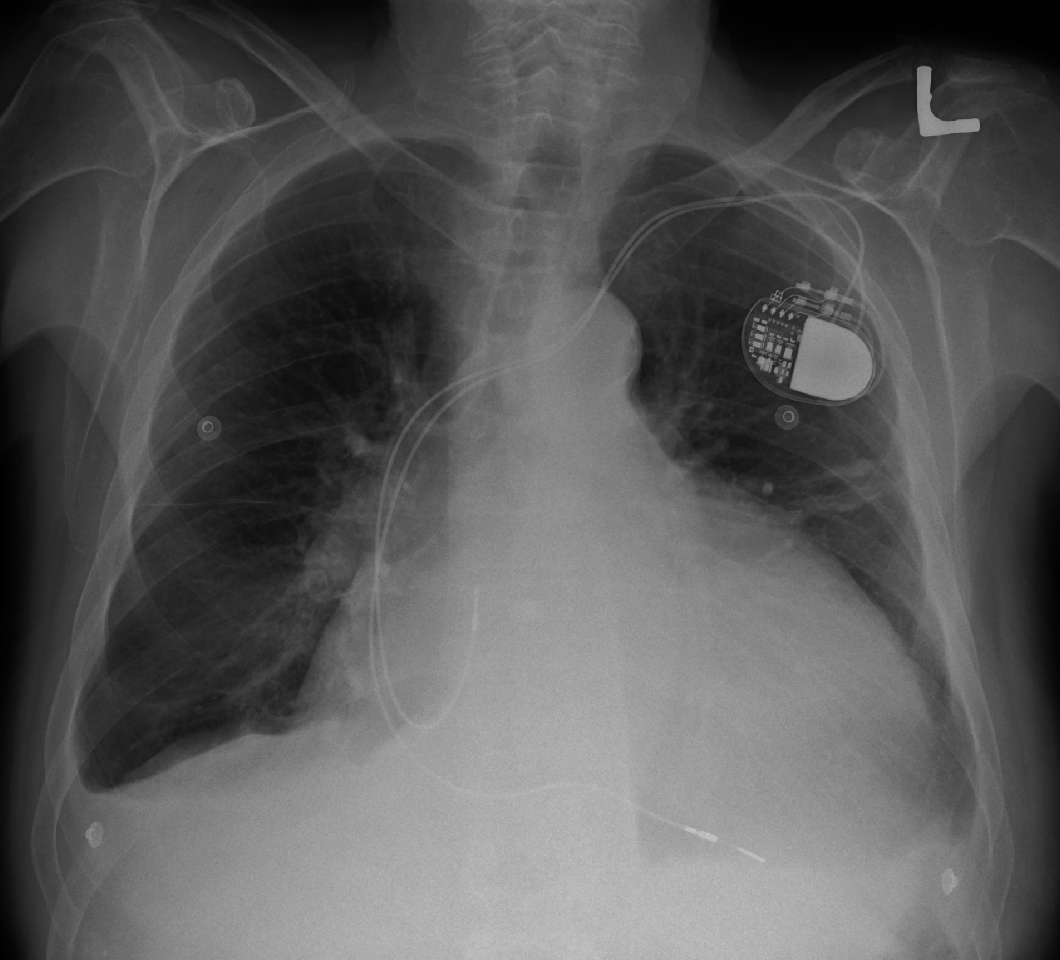

In comparison with the study of ___, there is little overall change. Again there is substantial enlargement of the cardiac silhouette with a dual-channel pacer device in place. No evidence of vascular congestion or acute focal pneumonia. Blunting of the costophrenic angles is again seen.